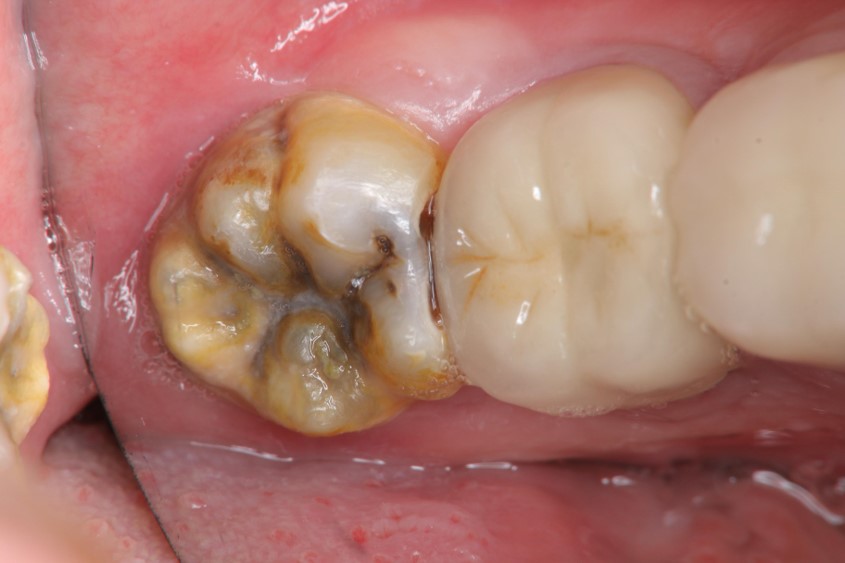

治療前,左下阻生齒深度蛀牙